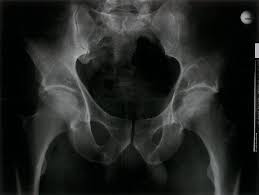

Made worse by movement), fracture. Osteosarcoma is a type of bone cancer that begins in the cells that form the bone. In pelvic bone cancer, when the size of the tumor increases it puts enormous amounts of pressure upon the bones. There are no warning signs of early prostate cancer. Stage 0 (zero) and stages i through iv (1 through 4).

Women with ovarian cancer can experience back pain when fluid accumulates in the pelvis or when the tumor spreads in the abdomen or pelvis, directly irritating tissue in the lower back, says marleen. The macmillan cancer support website has more information about secondary bone cancer. Made worse by movement), fracture. Usually, the pain may come and go, and over days, it will. However, osteosarcoma can develop in any bone, including the bones of the pelvis (hips), shoulder, and jaw. Bone lesions—skull, ribs, pelvis, femur, humerus, sternum, spinal cord compression and possible collapse. There are two types of bone cancer: Primary bone cancer is a rare type of cancer that begins in the bones. Your pelvic area is the lower portion of the trunk of your body. Primary bone cancer develops in the bones. Bowel obstruction when there is a blockage in the bowel. However, it might also develop in supporting soft tissue, such as. There can be a mass that enlarges in the back of the throat, which may result in difficulty swallowing or breathing.

Osteosarcoma Physiopedia from www.physio-pedia.com When these cancers in the bone are looked at under a microscope, they look like the tissue they came from. Certain types emerge most often in the long bones of the arms and legs, while others occur most often in the pelvis, legs, ribs, and spine. However, the symptoms will start showing from an early age before a final diagnosis is made. Bone cancer occurring in the pelvis may cause lower back pain and sciatica. Bone cancer signs and symptoms. When to see your doctor about prostate cancer symptoms. How is bone cancer diagnosed? It can grow in any of the bones in the body.

Signs of visceroptosis) the tumor should be suspected. General information about transitional cell cancer of the renal pelvis and ureter. Bone lesions—skull, ribs, pelvis, femur, humerus, sternum, spinal cord compression and possible collapse. Bone cancer signs and symptoms. When to see your doctor about prostate cancer symptoms. There are no warning signs of early prostate cancer. Ewing sarcoma of the bone develops in the axial skeleton, which includes the pelvis, ribs, spine and skull. Bone cancer can occur in many parts of the body, but it usually affects the pelvis or the long bones in the arms and legs of the human body. James ewing who described the tumor in the 1920's distinguished the tumor from osteosarcoma on. Cancer of the renal pelvis or ureter is cancer that forms in the kidney's pelvis or the tube (ureter) that carries urine from the kidney to the bladder. With osteosarcoma, cancerous cells produce bone, generally in the bones of the arm or leg. This spread of cancer is called a metastasis and can form a secondary cancer in another organ. Bone pain, tenderness (especially back, ribs;